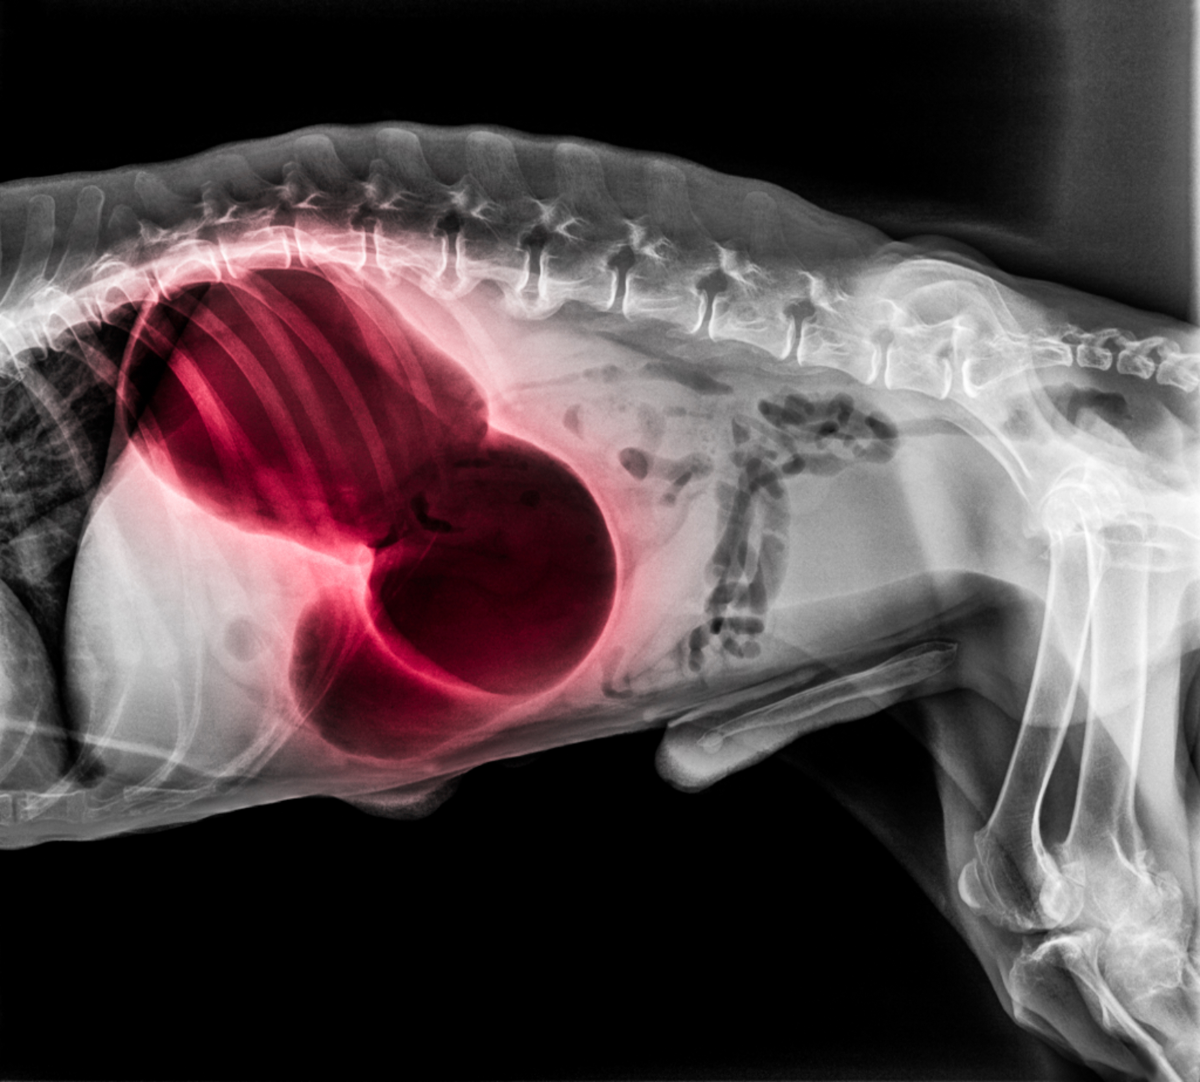

Der Tierarzt macht zunächst ein Röntgenbild, um eine eindeutige Diagnose zu stellen. Anschließend stabilisiert er das Tier mithilfe von Infusionen und bereitet es für die Notoperation vor.